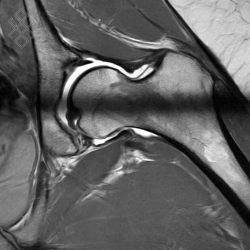

Arthro-IRM de la Hanche